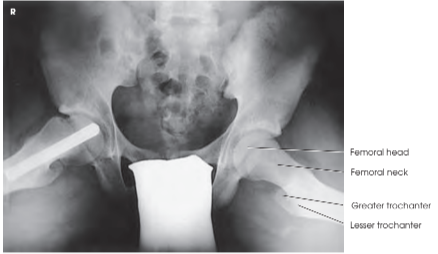

Modified Cleaves Method를 사용한 AP 사선 촬영은 **골반(pelvis)**과 **대퇴골 경부(femoral neck)**의 oblique 영상을 제공합니다. 이 방법은 다음과 같은 구조가 명확하게 보여야 합니다:

- 비틀림 없이 대칭적인 골반

- 절구(acetabulum), 대퇴골두(femoral head), 및 **대퇴 경부(femoral neck)**의 선명한 표시

- 과도한 벌림으로 인해 대퇴골 대전자(greater trochanter)가 경부를 가리지 않아야 합니다.